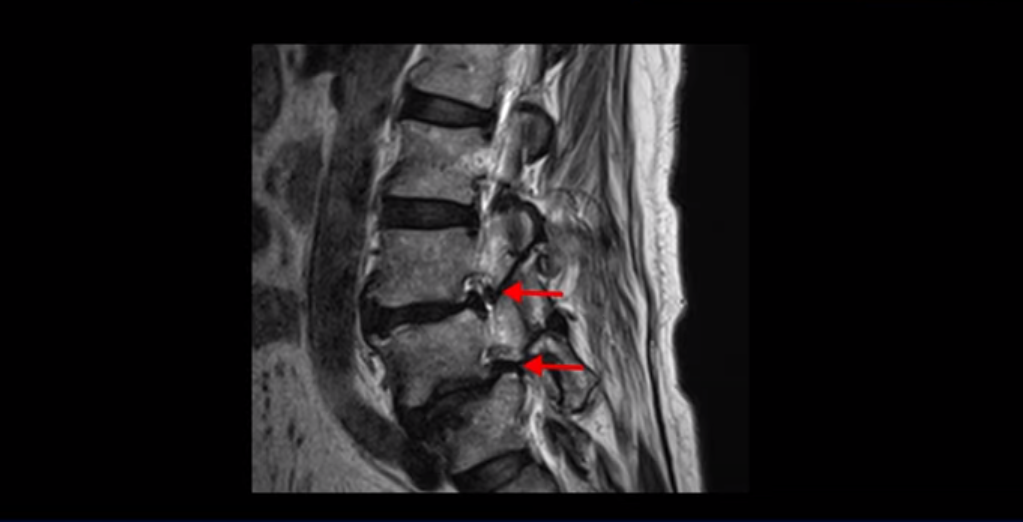

제가 이분 MRI 보면서 설명 드린 후 어떻게 대학병원에서 나사 6개 박는 수술밖에 방법이 없다고 들은 전방전위와 협착증 환자가 비수술 근육재활치료로 좋아질 수 있는지, 치료는 어떻게 하는 건지 자세히 설명 드리도록 하겠습니다.

MRI를 보면 보시다시피 전방전위가 2마디가 있는데, 4번 5번 마디는 2단계로 매우 심합니다.

이렇게 전방전위가 있으면 신경 구멍을 좁히게 되니까 협착이 다른 사람에 비해 더 쉽게 올 수 있습니다. 그래서 오른쪽 신경 구멍을 보면 3번 4번, 4번 5번 추간공이 많이 좁아져 있습니다.

왼쪽 신경 구멍도 두 마디가 좁아져 있어서

이분은 오른쪽, 왼쪽 양쪽 엉덩이와 다리가 다 저리고 아파 못 걷습니다. 이렇게 전방전위와 협착도 심하니까 국내 최상급 대학병원에서도 나사 6개 박는 유합술을 반드시 해야 한다는데, 어떻게 이런 상태가 수술 없이 치료가 가능할까요? 지금부터 설명 드립니다.